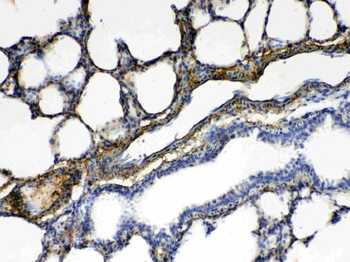

10 μg, 100 μg - Anti-CD44 Antibody [orb402179]

ELISA, FC, ICC, IF, IHC, IHC-Fr, WB

Human, Mouse, Rat

Rabbit

Polyclonal

Unconjugated

10 μg, 100 μg - Anti-PRDM1/Blimp1 Antibody [orb402200]